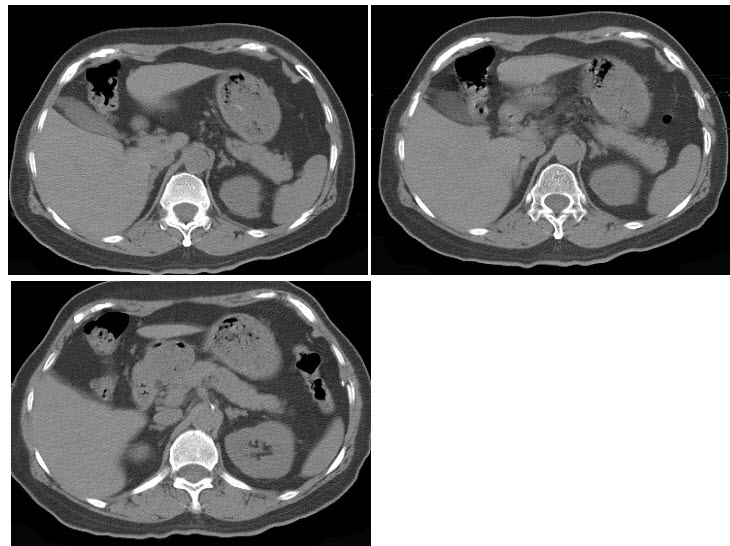

男,56岁,无痛性全程血尿1月,CT平扫及增强检查如图,下列说法正确的是()

A.右肾上极,肾脏局部隆起,平扫时其密度与肾相近,不易分辨其轮廓

B.增强扫描皮质期,病灶强化明显,但仍低于肾皮质的强化

C.增强扫描实质期,病灶强化迅速减退,可清楚的分辨其轮廓

D.右肾静脉及下腔静脉内未见充盈缺损影

E.考虑为右肾上极的肾癌